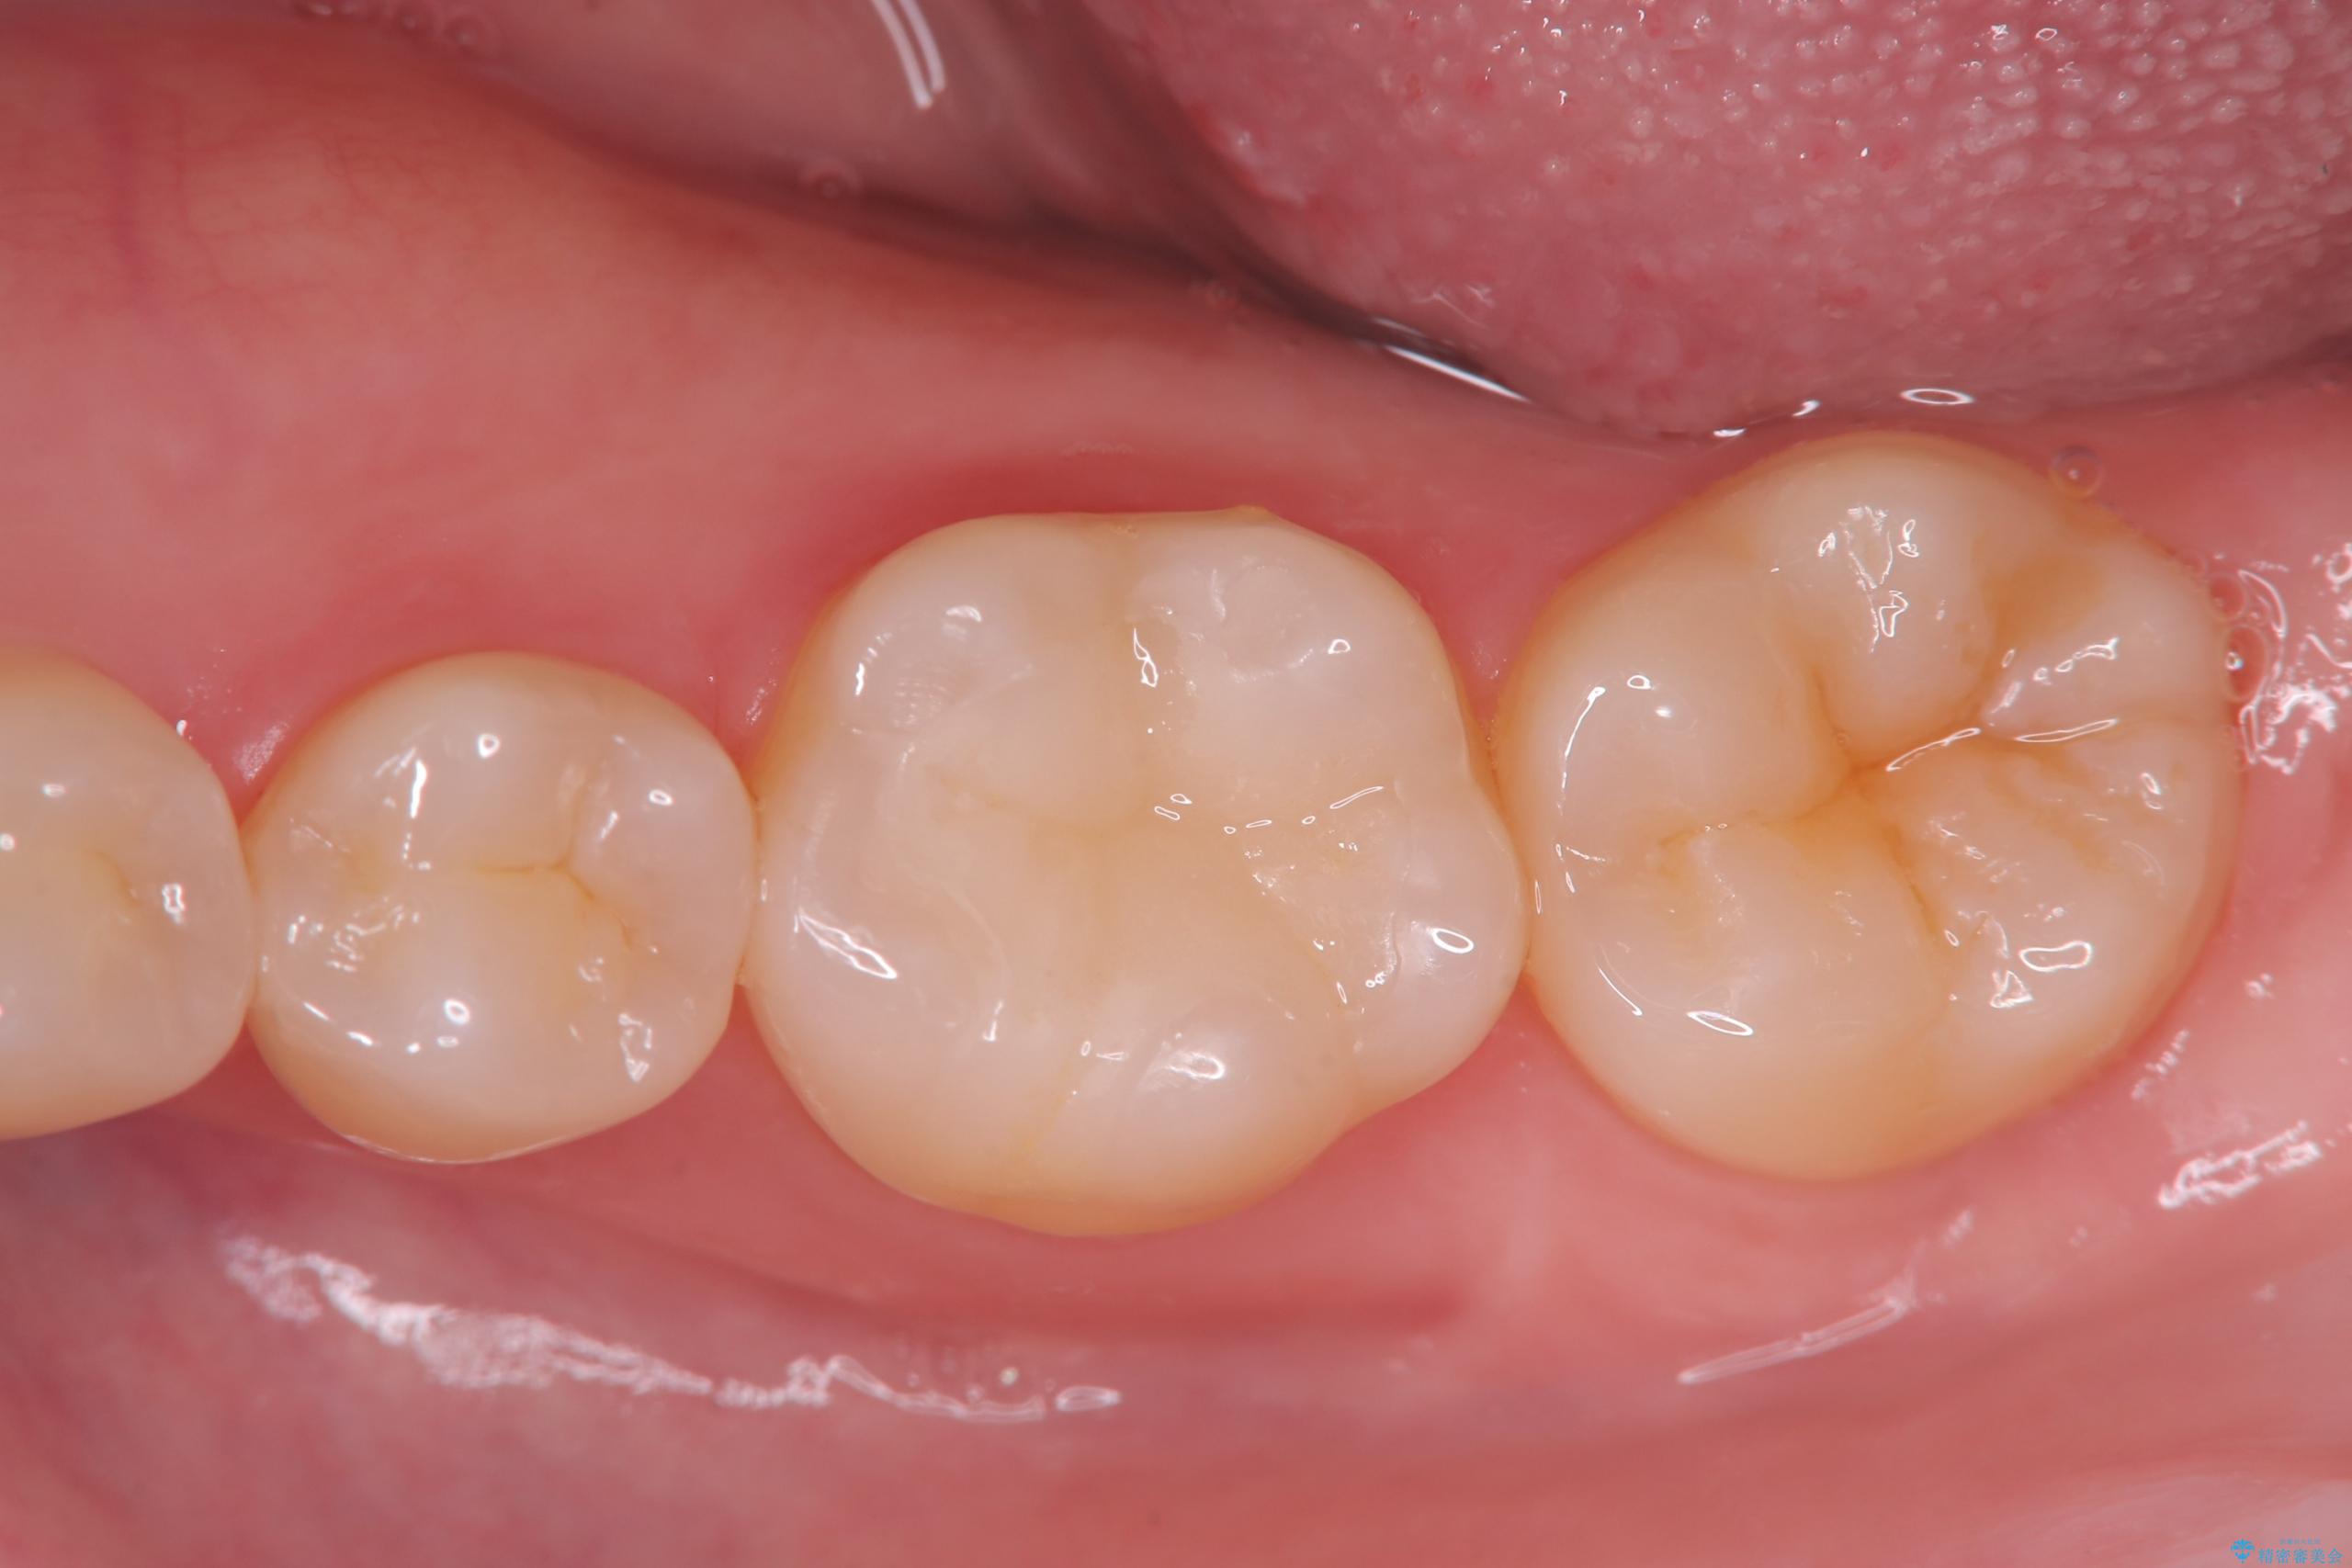

今回は、経年的な劣化が少なく、汚れが付着しにくいセラミックインレーを用いて治療を行いました。

セラミックインレー装着時には、唾液が入らないようラバーダムシートを使用し、接着精度を高めることで、長く安心して使っていただける治療を心がけています。